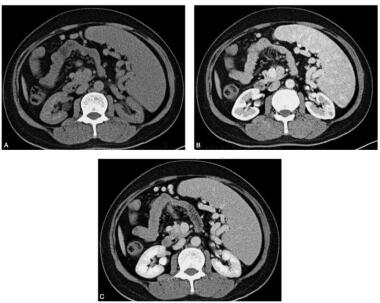

患者,女性,27岁,主诉:体检发现脾大占位性病变1周。病来患者无腹痛、腹胀,无发热,无齿龈出血。否认肝炎、结核病史。查体:皮肤及巩膜无黄染,腹软,无压痛,无反跳痛及肌紧张,未触及局部包块,脾肋下2cm可触及,边界清楚,质韧、活动可,无触痛,移动性浊音(-)。血常规:WBC:8.4×109/L,RBC:4.1×1012/L,PLT:125×109/L。CT增强,平扫显示脾脏增厚,其内多发稍低密度肿块影,与脾脏实质分界欠清楚,动脉期肿块强化不明显,边缘似见强化,静脉期强化仍低于周围正常组织(图2)。

图2 CT增强扫描:术前诊断脾脏淋巴瘤。平扫脾脏增厚,其内多发稍低密度肿块影,与脾脏实质分界欠清楚,动脉期肿块强化不明显,边缘似见强化,静脉期强化仍低于周围正常组织